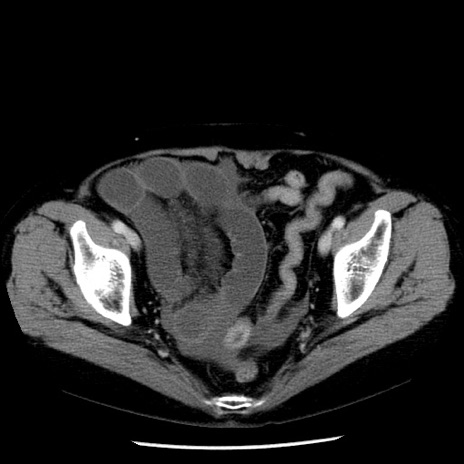

症例13(横断像)

【症例】70歳代女性

【主訴】腹痛、嘔吐

【現病歴】15時間程前(昨晩)より腹痛あり。今朝になっても症状の改善なく、嘔吐あり。腹痛も増悪あり、救急外来受診。

【既往歴】子宮癌全摘術後

【身体所見】意識清明、BP 121/72mmHg、P 74bpm、SpO2 100%(RA)、腹部:平坦・軟、腸雑音ほぼ聴取せず。下腹部・心窩部・臍左上に圧痛あり。反跳痛なし。

【データ】WBC 10600、CRP 0.15